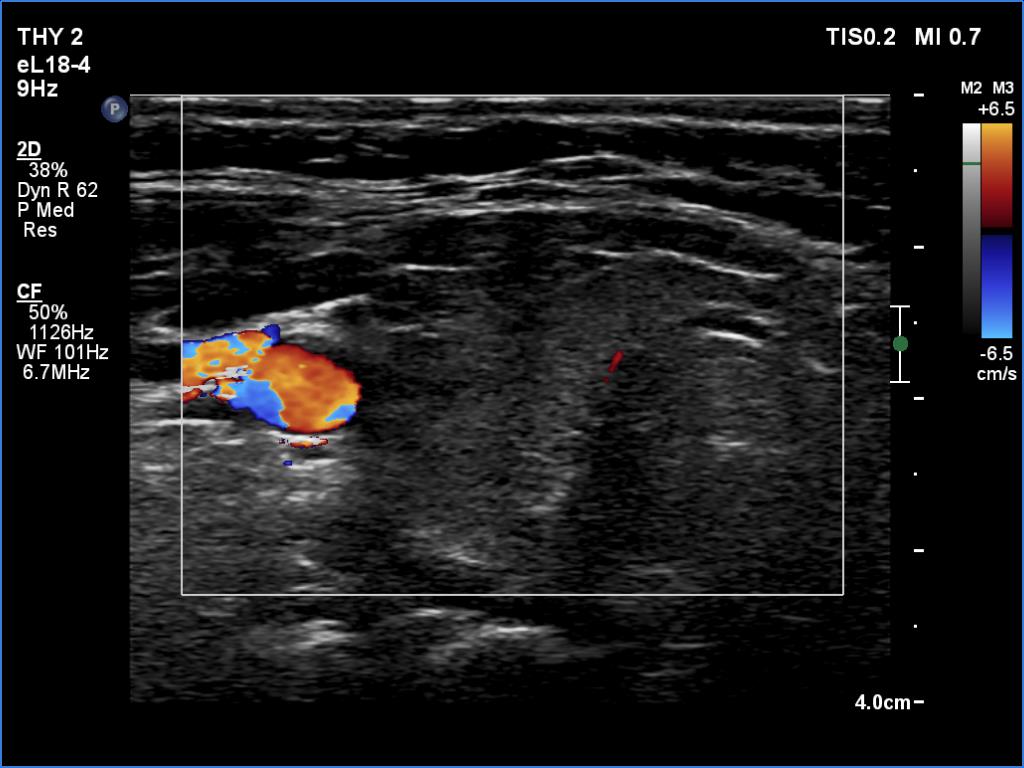

Right lobe, transverse scan, color Doppler mode. The lobe is avascular.